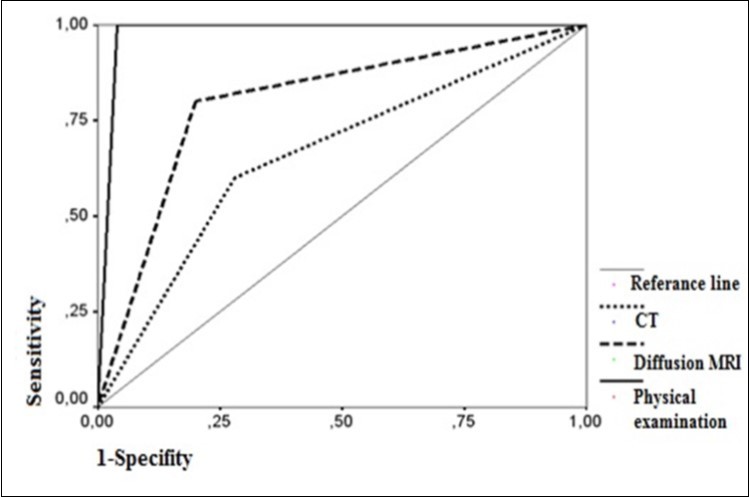

20 of 24 (83.3%) patients who had signs of cholesteatoma on preoperative diffusion MRI were positive intraoperatively while the remaining 4 (16.7%) were negative. 5 of 9 (55.4%) patients who had no evidence of cholesteatoma on MRI were positive intraoperatively while 4 (44.4%) were not (Table 1). There was no significant result obtained in terms of impact of diffusion MRI on detecting intraoperative cholesteatoma (p=0.09). In terms of indicatory strength of positive physical examination findings over presence of intraoperative cholesteatoma, sensitivity was found to be 96% whereas specifity was 87.5%, positive predictive value was 96% and negative predictive value was 87.5%. The area below the curve on ROC curve analysis was calculated as 98% (Table 3) (Figure 4).

Figure 4.ROC curves of PE, CT and diffusion MRI

When the impact of positive MRI findings on detecting cholesteatoma was concerned, sensitivity was found to be 80% whereas specifity was 50%, positive predictive value was 83.3% and negative predictive value was 44.4%. The area below the curve on ROC curve analysis was calculated as 80% (Table 3) (Figure 4). When the impact of tomographic view of bone erosion on detecting cholestatoma was investigated, sensitivity was found to be 72% whereas specifity was 37%, positive predictive value was 78% and negative predictive value was 30%. The area below the curve on ROC curve analysis was calculated as 66% (Table 3) (Figure 4).